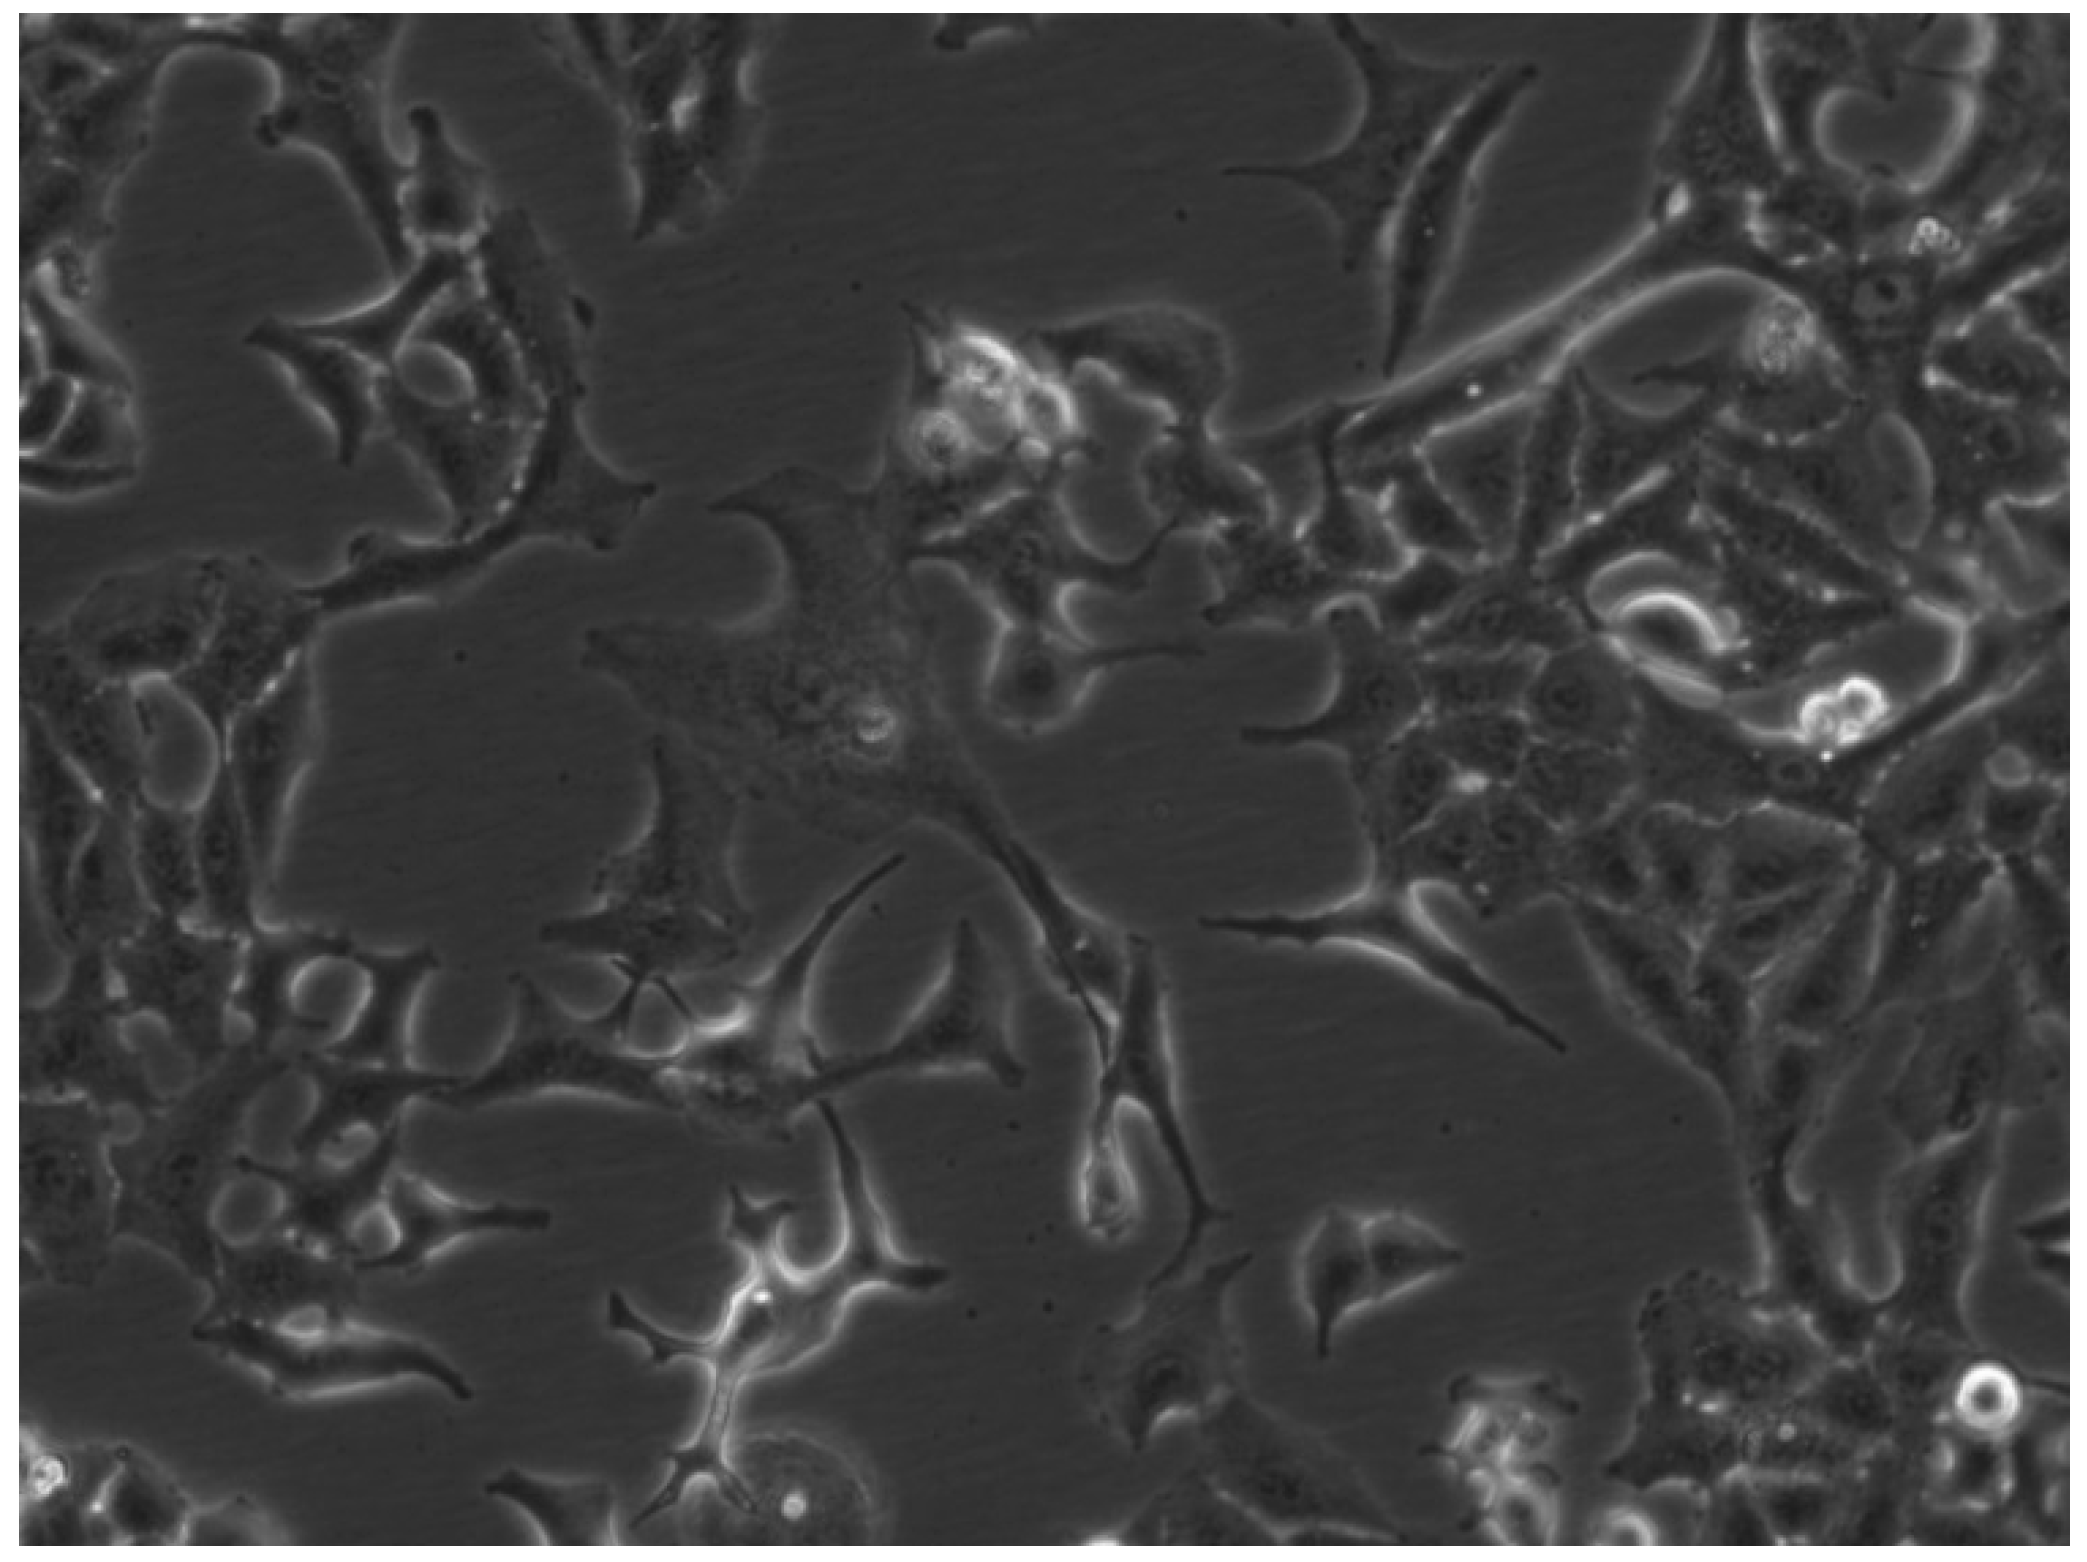

2.7.1. A549 Cell Line

2.7.2. MCF-7 Cell Line